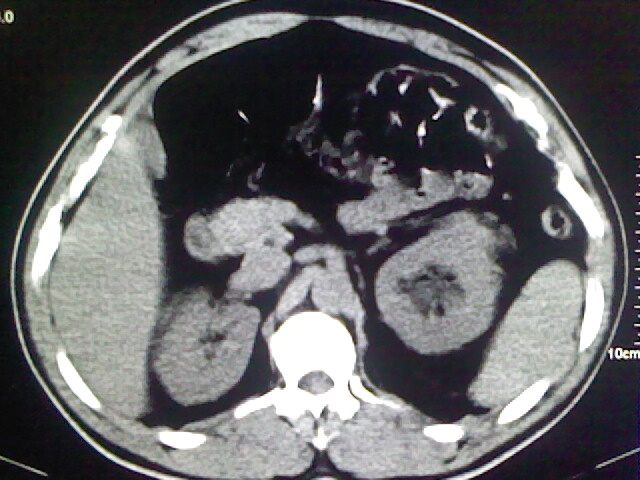

以下是引用zsl6918在2009-2-7 7:29:00的发言:[br]请提供介入的方式方法,肾及输尿管改变考虑与介入损伤有关,漏了,尿液外渗。

以下是引用余辉在2009-2-7 8:27:00的发言:[br]可能是硬化剂烧穿囊壁进入肾盂输尿管了,尿漏。不除外介入或碎石术后合并感染[br]患者术后怀疑结石,接着就碎石了?就怀疑没有确诊吗?碎石用的什么方法?气压弹道还是体外超声?如果这样的话责任人都难找

以下是引用随光逐影在2009-2-7 8:46:00的发言:[br]支持3楼意见。[br]另:不排除左肾及肾周感染可能。